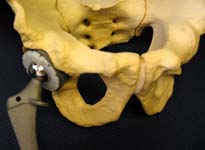

However, for patients with severe arthritis, the pain may not respond to those kinds of interventions. Patients with severe arthritis sometimes can benefit from total hip replacement surgery (See Figures 5 and 6).

Patients with severe arthritis who have tried the above remedies sometimes can benefit from total hip replacement surgery.

Surgery

Hip replacement is a surgical procedure that decreases pain and improves the quality of life in many patients with severe arthritis of the hips.

Typically, patients undergo this surgery after non-operative treatments (such as activity modification anti-inflammatory medications or hip joint injections) have failed to provide relief of arthritic symptoms.

Surgeons have performed hip replacements for over four decades ,generally with excellent results. Most reports have ten-year success rates in excess of 90 percent.